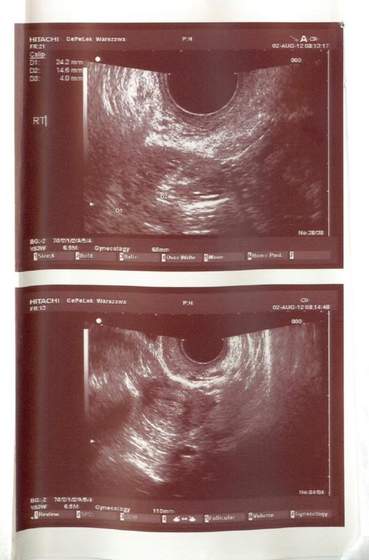

Nie mierzyłam tempki bo pewnie i tak by była zaburzona bo alkohol itd... @ dalej nie ma... znowu ten cykl się wydłuża... Wrr